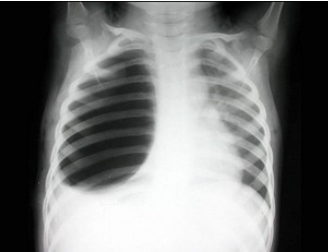

184、单项选择题

女,9岁,呼吸困难半月余,结合图像,最可能的诊断是()

A.气胸

B.胸腔积液

C.肺大泡

D.液气胸

E.肺气肿